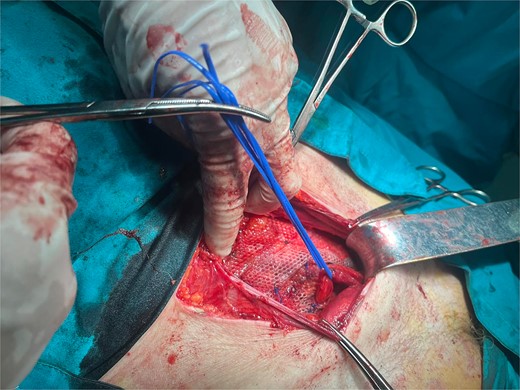

A 72-year-old patient, in good physical condition with a BMI of 26.1, came for an examination due to swelling in the right lateral abdominal wall without swelling of the scrotum. The patient was operated on for a right-sided inguinal hernia as an 8-year-old boy, but there was no appropriate medical documentation for the operative technique used. A month ago, besides the swelling, he experienced occasional abdominal pain and difficulties during physical activities in his garden. During clinical examination, a soft swelling in the right lateral abdominal wall, compressible under palpation was ascertained (Fig. 1). The abdominal ultrasound and contrast abdominal CT showed a thinned right abdominal wall with superficial intestinal loops and the differential diagnosis of a large recurrent inguinal or Spigelian hernia was presumed (Fig. 2). The patient received one dose of prophylactic cephalosporin preoperatively, and was operated on under general endotracheal anesthesia, in a supine position with a lumbar pillow placed for a slight tilt to the left. A right lateral lumbar-inguinal skin incision 4–5 cm above the anterior superior iliac spine in a horizontal direction following the lumbar dermatomal lines was performed. Subcutaneous fat was gently separated and the hernial sac dissection went to its apex below the right costal arch and base to the deep inguinal opening. When the sac was completely freed, the final diagnosis of giant recurrent indirect inguinal hernia (Fig. 3), and the sac with its content was repositioned in the abdominal cavity without opening the abdominal cavity and partial closure of the internal iliac ring was performed with resorptive sutures. After the dissection of the inguinal ligament up to the pubic tubercle (without extending the skin incision) a 15 × 12 cm polypropylene mesh was placed (Fig. 4), fixed to the pubic tuberculum and conjoint tendon with a laparoscopic taker (Fig. 5), and the ileopubic ligament partly with individual and partly with continuous non-absorbable polypropylene 2/0 suture. An opening for the spermatic cord was provided and medially the mesh was fixed with individual resorptive stitches (Fig. 6). The aponeurosis of the external oblique muscle was closed as much as it allowed to be approximated followed by individual subcutaneous and skin stitches (Fig. 7). The operating time was 65 minutes without blood loss and the patient had a quick and satisfactory recovery. He was discharged from the hospital on the third post-op day, and the skin stitches were removed on the 14th day. One month after the surgical treatment the patient was in good condition without any complaints (Fig. 8).

Placement of the polypropylene mesh 15 × 12 cm after dissection of the spermatic cord